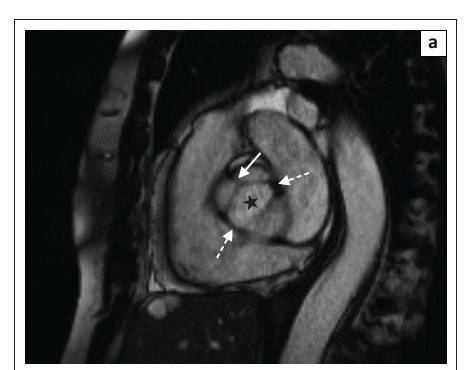

The most common leaflet abnormality of the aortic valve is a bicuspid aortic valve. The most common form of the bicuspid aortic valve is that of a valve with one raphe (Figure 6a) which is the result of fusion of two adjacent cusps.4 On rare occasions, the bicuspid valve is secondary to a bisinus valve, with only two sinuses of Valsalva and two cusps. No raphes are seen in these cases but the abnormality still results in the same characteristic 'fish mouth' opening of the valve (Figure 6b).